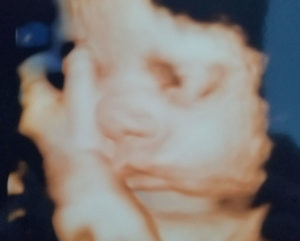

36 Weeks Pregnant With My Tubal Reversal Baby: C-section Scheduled Soon!

Third Trimester Going Well!

I am scheduled for C-section on 1/30/2018.

I am currently 36 weeks and 4 days pregnant.

This is my first pregnancy post reversal.

Patient age: 37

Tubal ligation type: Coagulation (burned)

Patient hometown: Marydel, Delaware